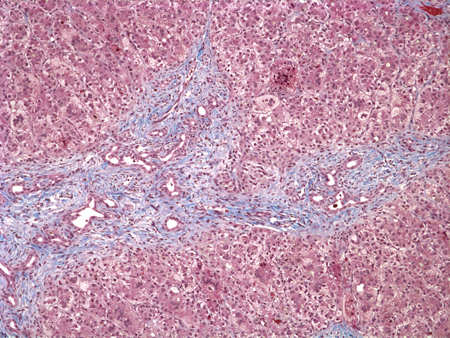

Biliary atresia

Liver biopsy specimen at the time of diagnosis reveals extensive fibrosis with bile duct and ductular proliferation and bile plugs

Pathology Department at The Children’s Hospital of Philadelphia